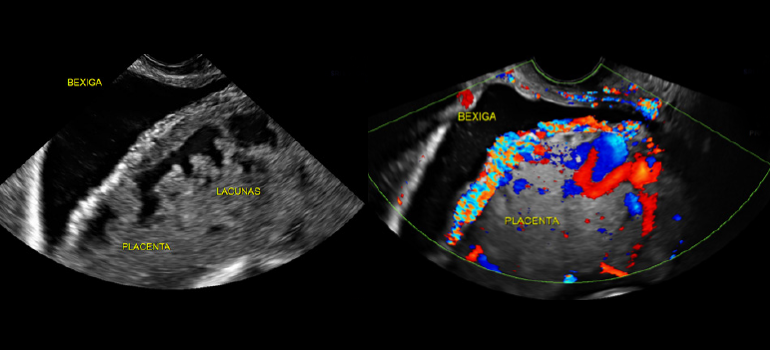

Múltiplas lacunas vasculares com bordas irregulares, fluxos turbulentos com elevadas velocidades e baixa resistência. Alguns estudos relatam que esse marcador possui a mais alta sensibilidade e valor preditivo positivo quando comparado aos outros marcadores. Quando múltiplas lacunas são vistas, em especial quatro ou mais, a associação com placenta acreta tem sido relatada de 100% em alguns estudos.

Anormalidades na interface serosa uterina – parede posterior da bexiga que incluem interrupção, espessamento, irregularidade, abaulamento da placenta na parede posterior da bexiga ou aumento da vascularização ao mapeamento com Doppler colorido.

Aumento da vascularização placentária ao Doppler colorido e a visualização de vasos conectando a placenta à bexiga com alto fluxo sanguíneo arterial diastólico também é sugestivo de invasão placentária. A sensibilidade do Doppler colorido para o diagnóstico do acretismo placentária se situa entre 86% e 100% e a especificidade entre 94% e 92%.